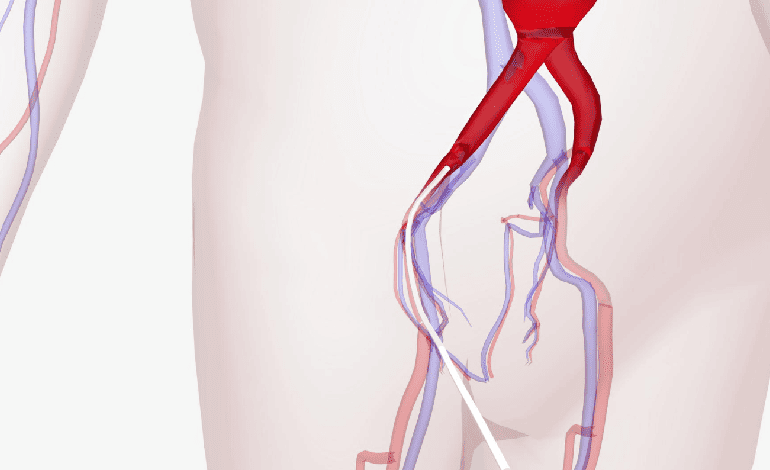

Angioplastias arteriales y venosas en Guadalajara - Innovación en Salud Vascular

¿Te preocupa la salud de tus vasos sanguíneos? Descubre soluciones avanzadas para una circulación óptima.